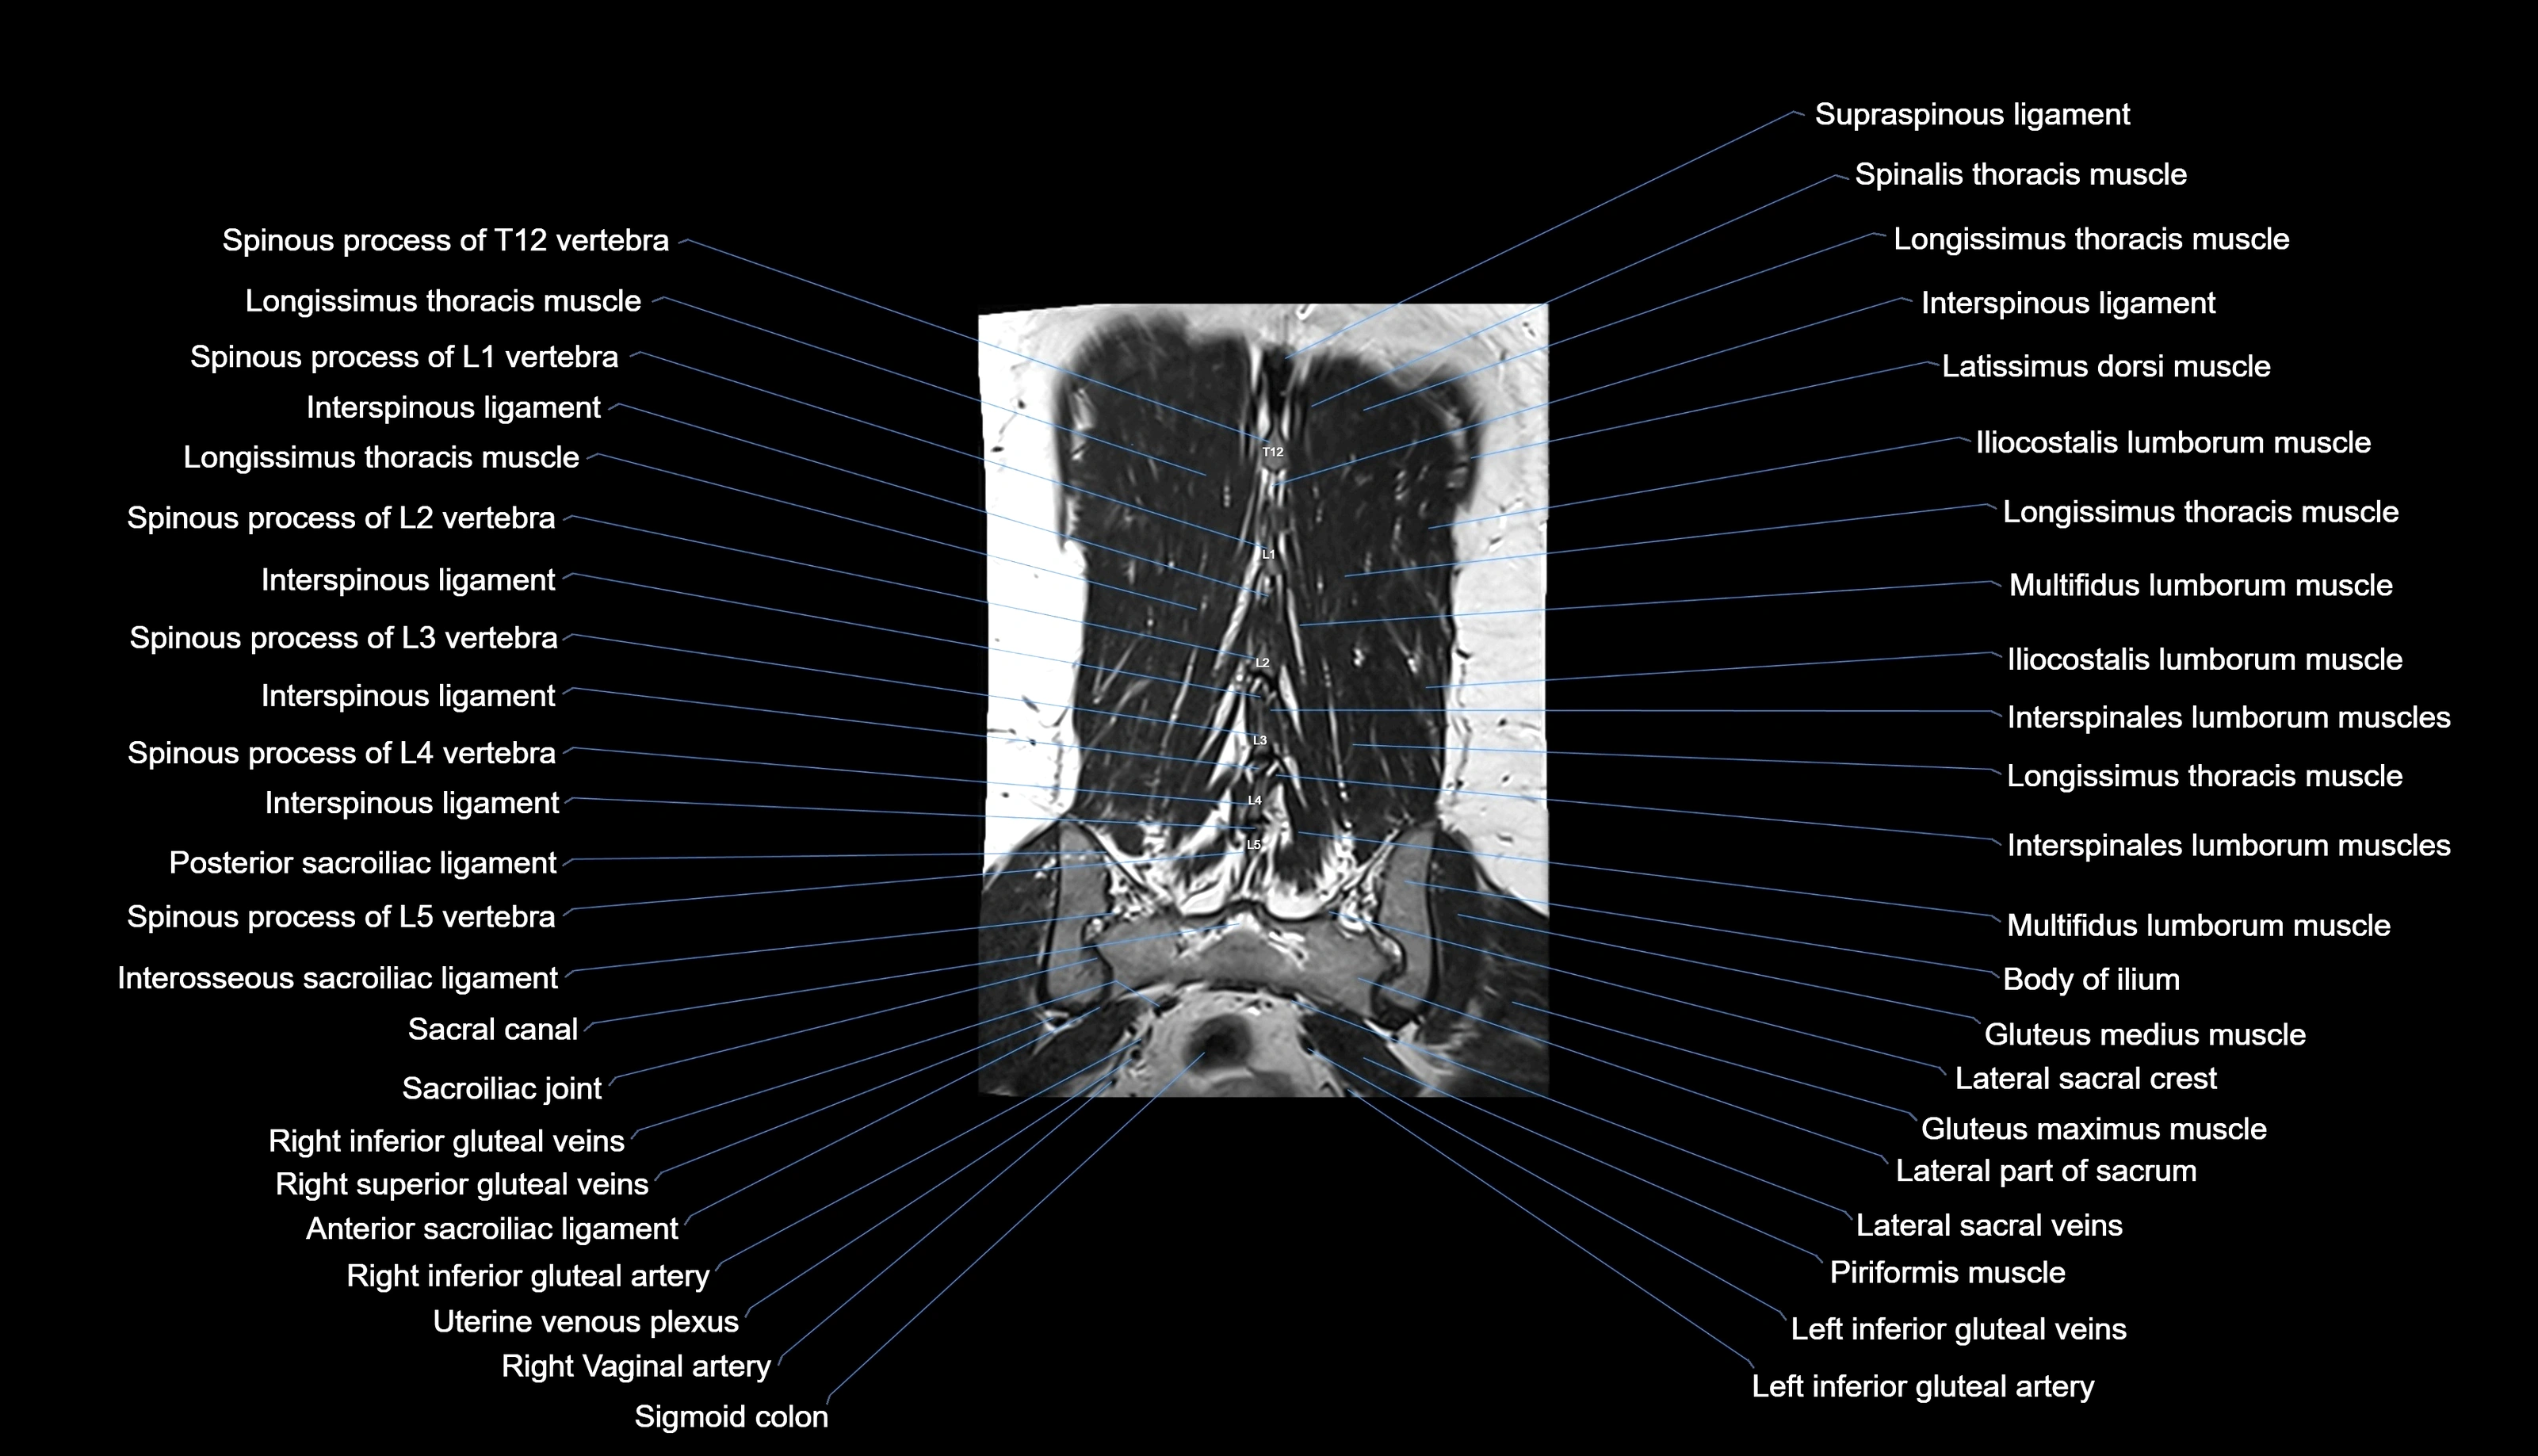

MRI images